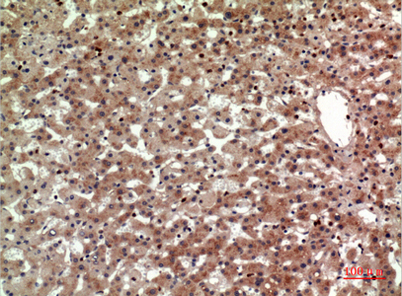

Product name: CD294 rabbit pAb

Dilutions: Western Blot: 1/500 - 1/2000. IHC-p: 1/100-1/300. ELISA: 1/20000. Not yet tested in other applications.

Immunogen: The antiserum was produced against synthesized peptide derived from the Internal region of human PTGDR2. AA range:161-210